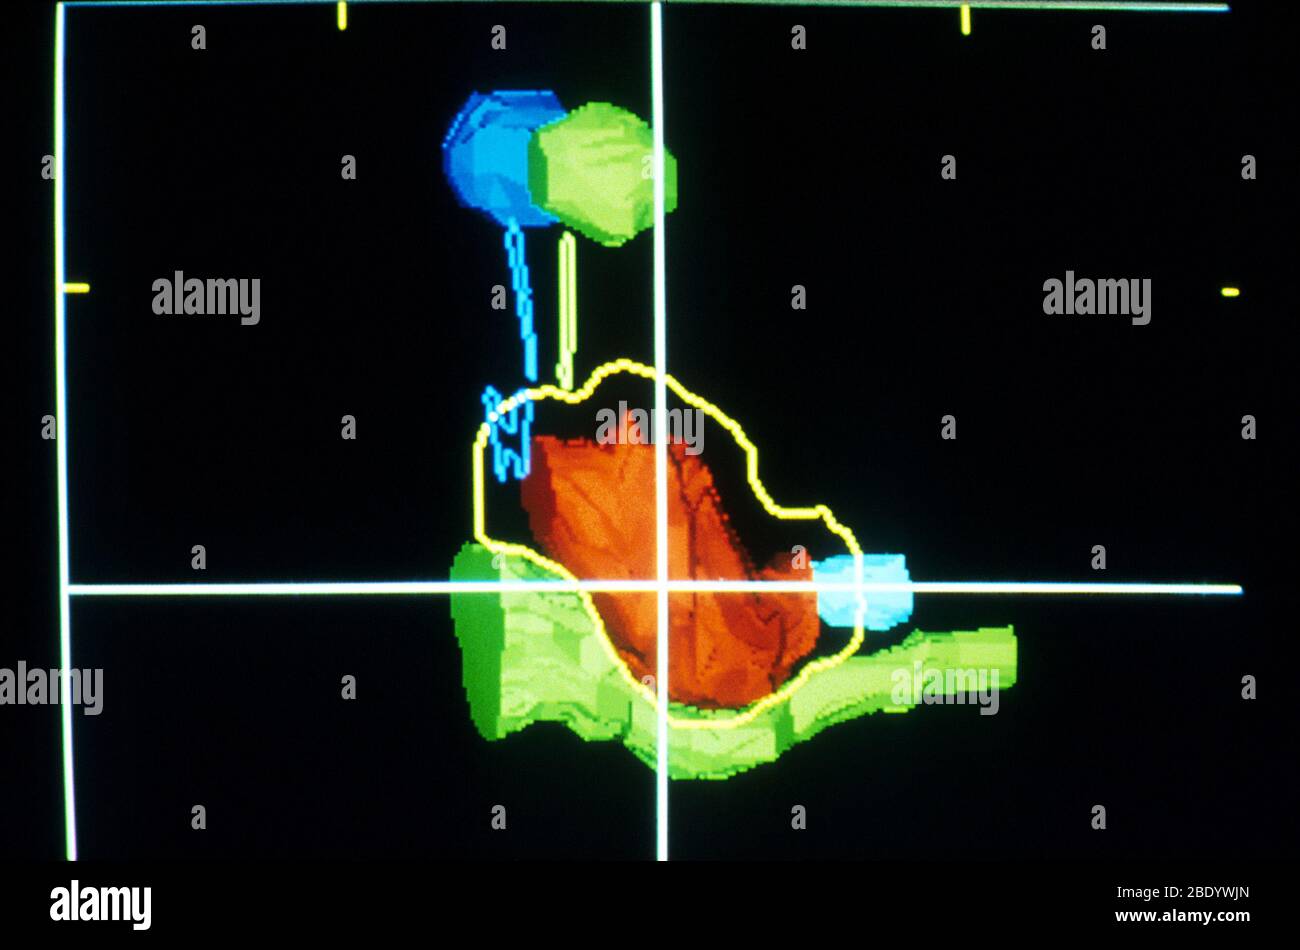

Faisceau de protons du cerveau pendant l'acquisition CT Banque D'Imageshttps://www.alamyimages.fr/image-license-details/?v=1https://www.alamyimages.fr/faisceau-de-protons-du-cerveau-pendant-l-acquisition-ct-image352810717.html

Faisceau de protons du cerveau pendant l'acquisition CT Banque D'Imageshttps://www.alamyimages.fr/image-license-details/?v=1https://www.alamyimages.fr/faisceau-de-protons-du-cerveau-pendant-l-acquisition-ct-image352810717.htmlRM2BDYWJN–Faisceau de protons du cerveau pendant l'acquisition CT